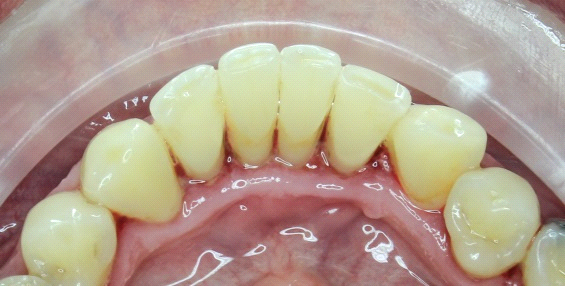

A dentálhigiénikus ezután hozzákezd a fogai tisztításához. Ultrahang segítségével eltávolítja a fogkövet, amely a fogakon megtapadt lepedék mineralizációja révén alakul ki, s amely idővel fogszuvasodást okoz. Az egész folyamat alapja, hogy az ultrahang megszünteti a fogkő tapadását, így az leesik. Mechanikus eltávolítás esetén kis kaparókat használ.

A lepedék és az elszíneződések (kávé, cigaretta, étel...) eltávolítására a szakember keféket, speciális fogkrémeket és “air flow” polírozást alkalmaz. Ez az eljárás szépen kifényesíti és megtisztítja a fogakat egy igen finom szemcsés anyag, víz és levegő keverékével.

Végül a fogzománca fluoridációja következik. Ennek köszönhetően a fogai ellenállóbbak és kevésbé érzékenyek lesznek, illetve friss leheletet eredményez. Az eljárás oldatok, gélek segítségével történik és teljesen fájdalommentes.